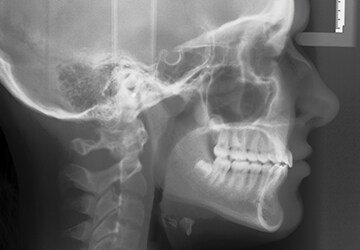

• Pre-treatment x-ray

• Post-treatment x-ray

An overbite is when the upper teeth cover the lower teeth when you bite down to a greater degree than normal. If it is not fixed, teeth may grind down and cause painful jaw problems down the road. Headgear is used to move teeth into place while also holding the jaw in place so it can grow in proper alignment with the upper teeth. Take a look at the difference it makes: